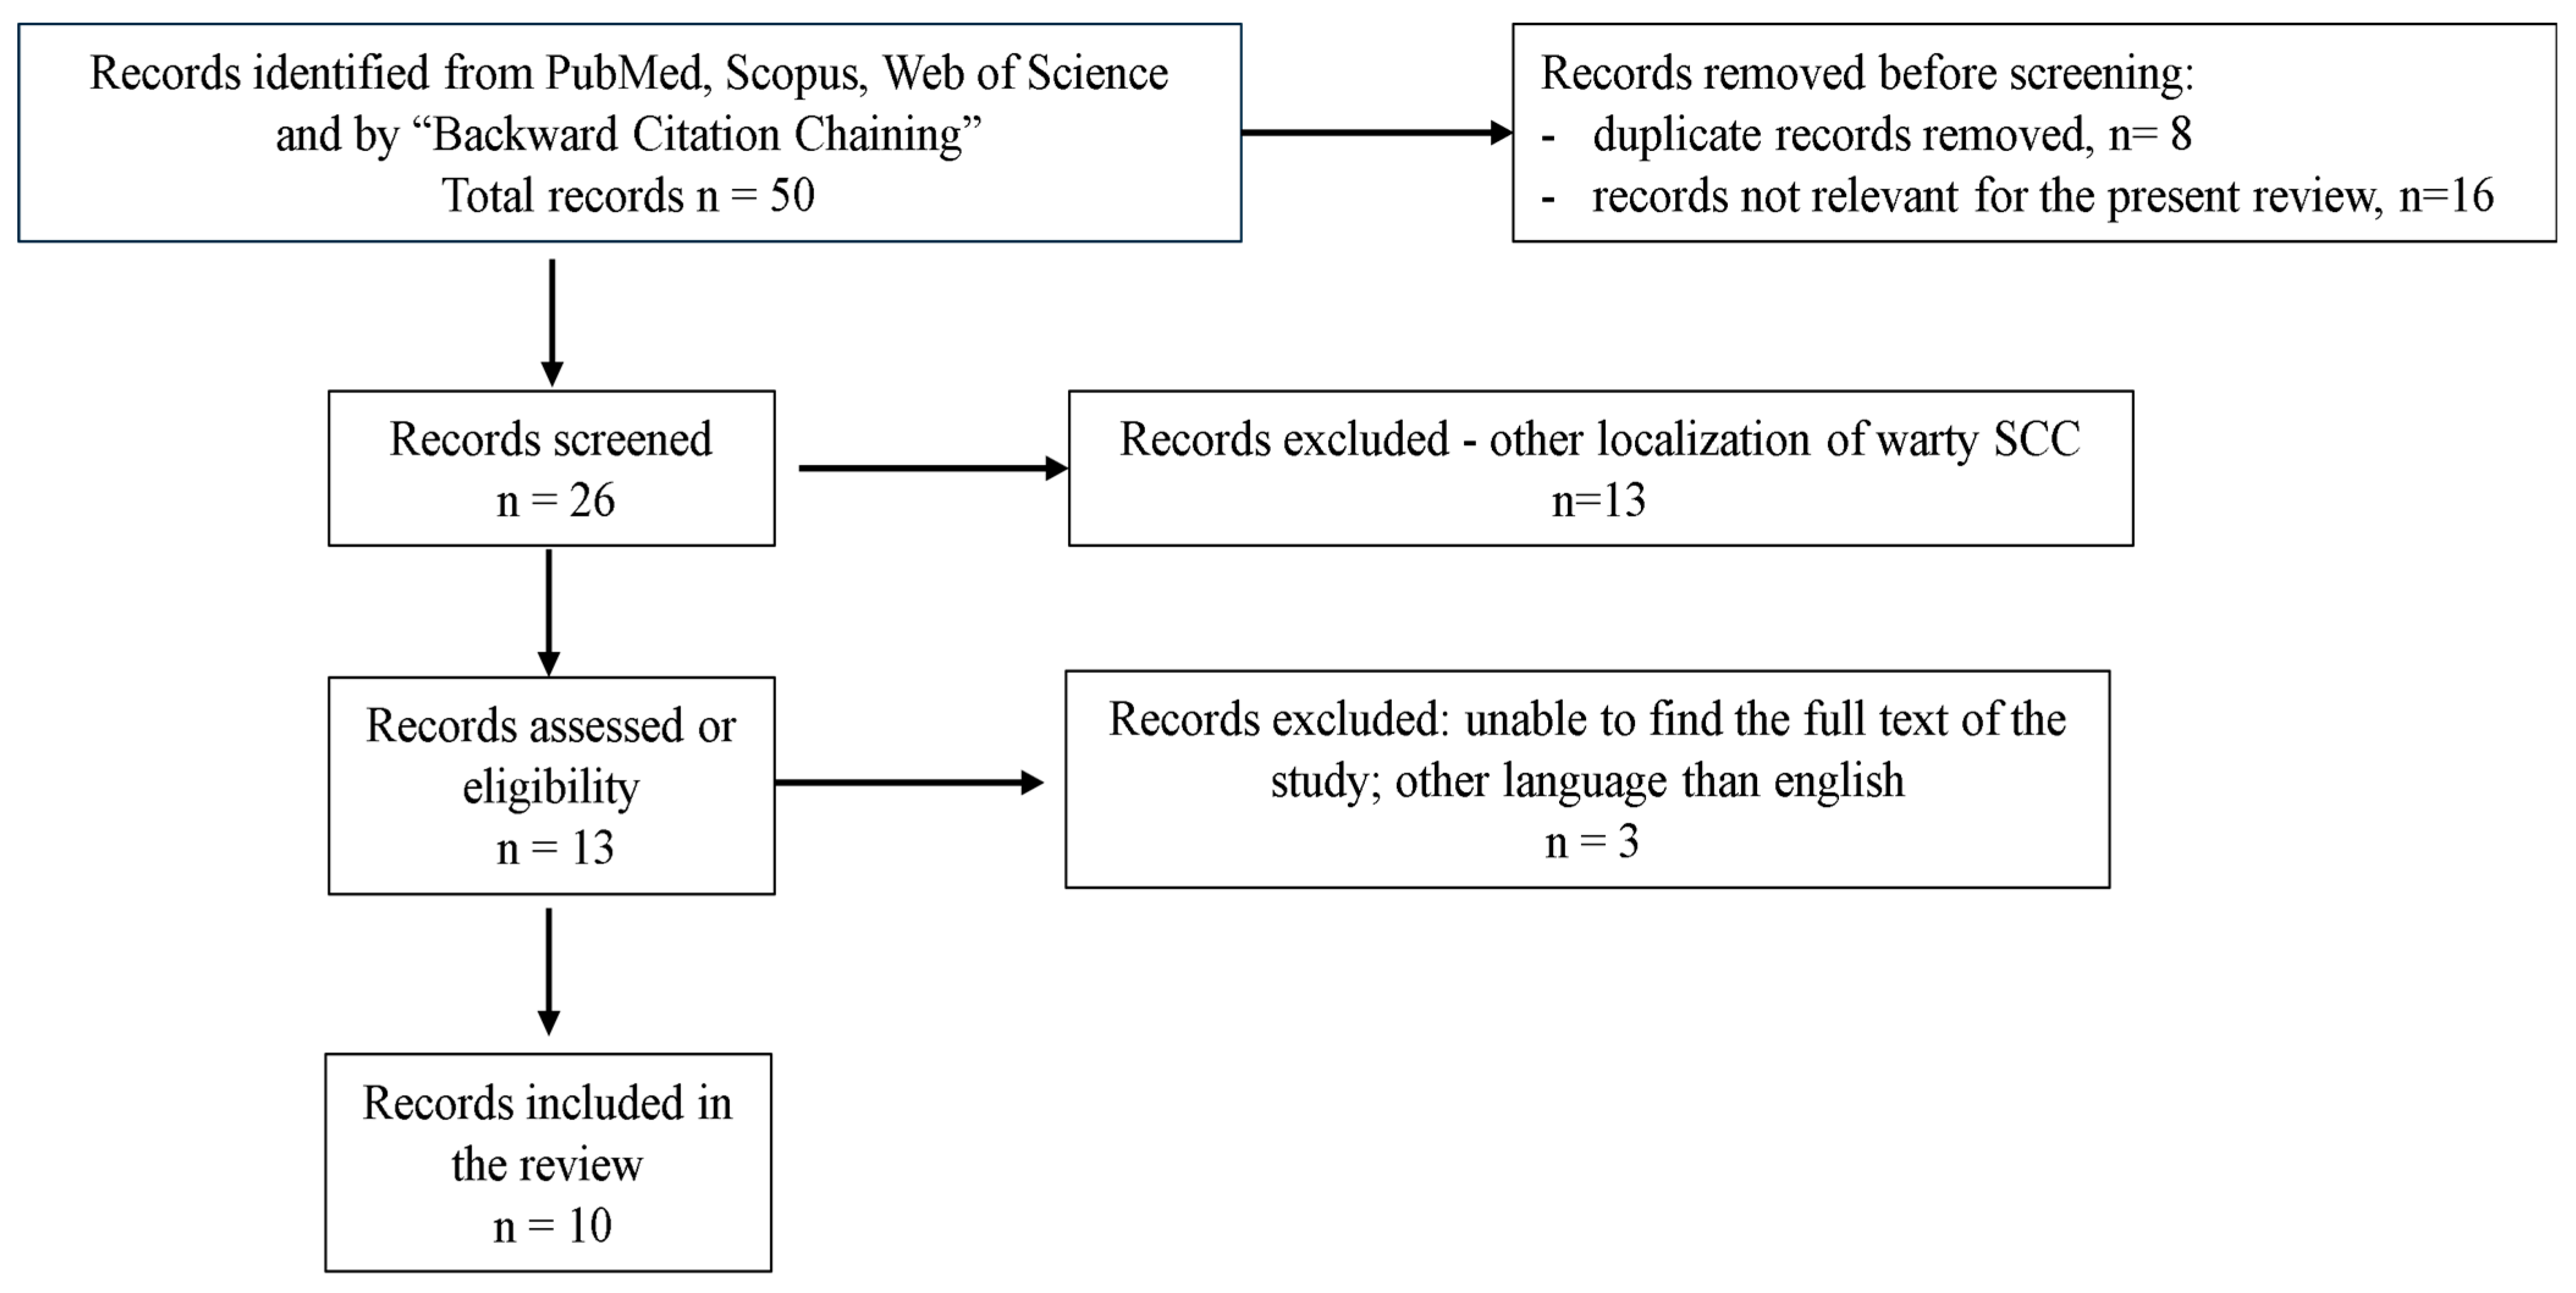

Literature Review